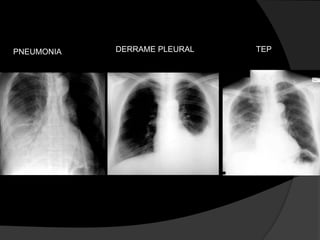

 Outras condições clínicas podem produzir

imagens radiológicas semelhantes ao

derrame pleural, de forma que estudos

PNEUMONIA DERRAME PLEURAL TEP